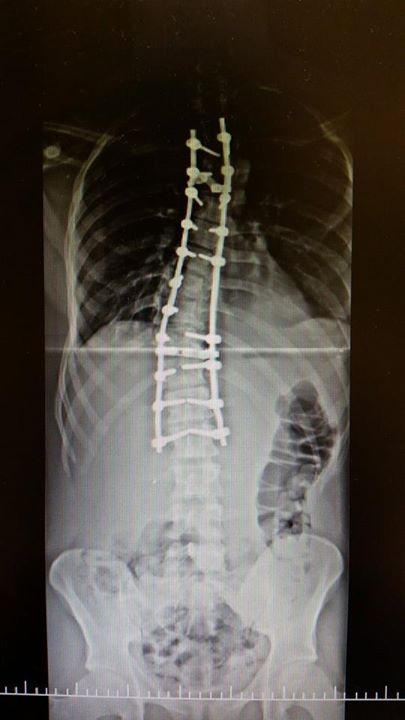

Imagens de pré e pós operatório de um caso de Escoliose:

Resultado final após a correção por via posterior.